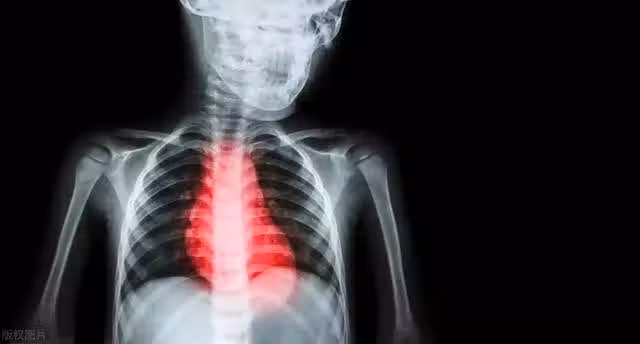

為什麼有人35歲心梗,有人100歲也不心梗?

儘管心梗通常發生在年齡較大的人身上,但現在越來越多的年輕人也開始出現心梗的病例,這與年輕人面臨的心理壓力有關。心理壓力可能來自於各種因素,例如工作壓力、人際關係、學習壓力等。

心理壓力還可能導致不良的生活方式,例如飲食不健康、缺乏運動、睡眠不足等,這些都是心血管疾病的危險因素。此外,年輕人的生活方式也往往與心血管疾病的發生有關,例如吸菸、酗酒、過度食用高脂肪食品等不良習慣,這些都可能增加心血管疾病的風險。